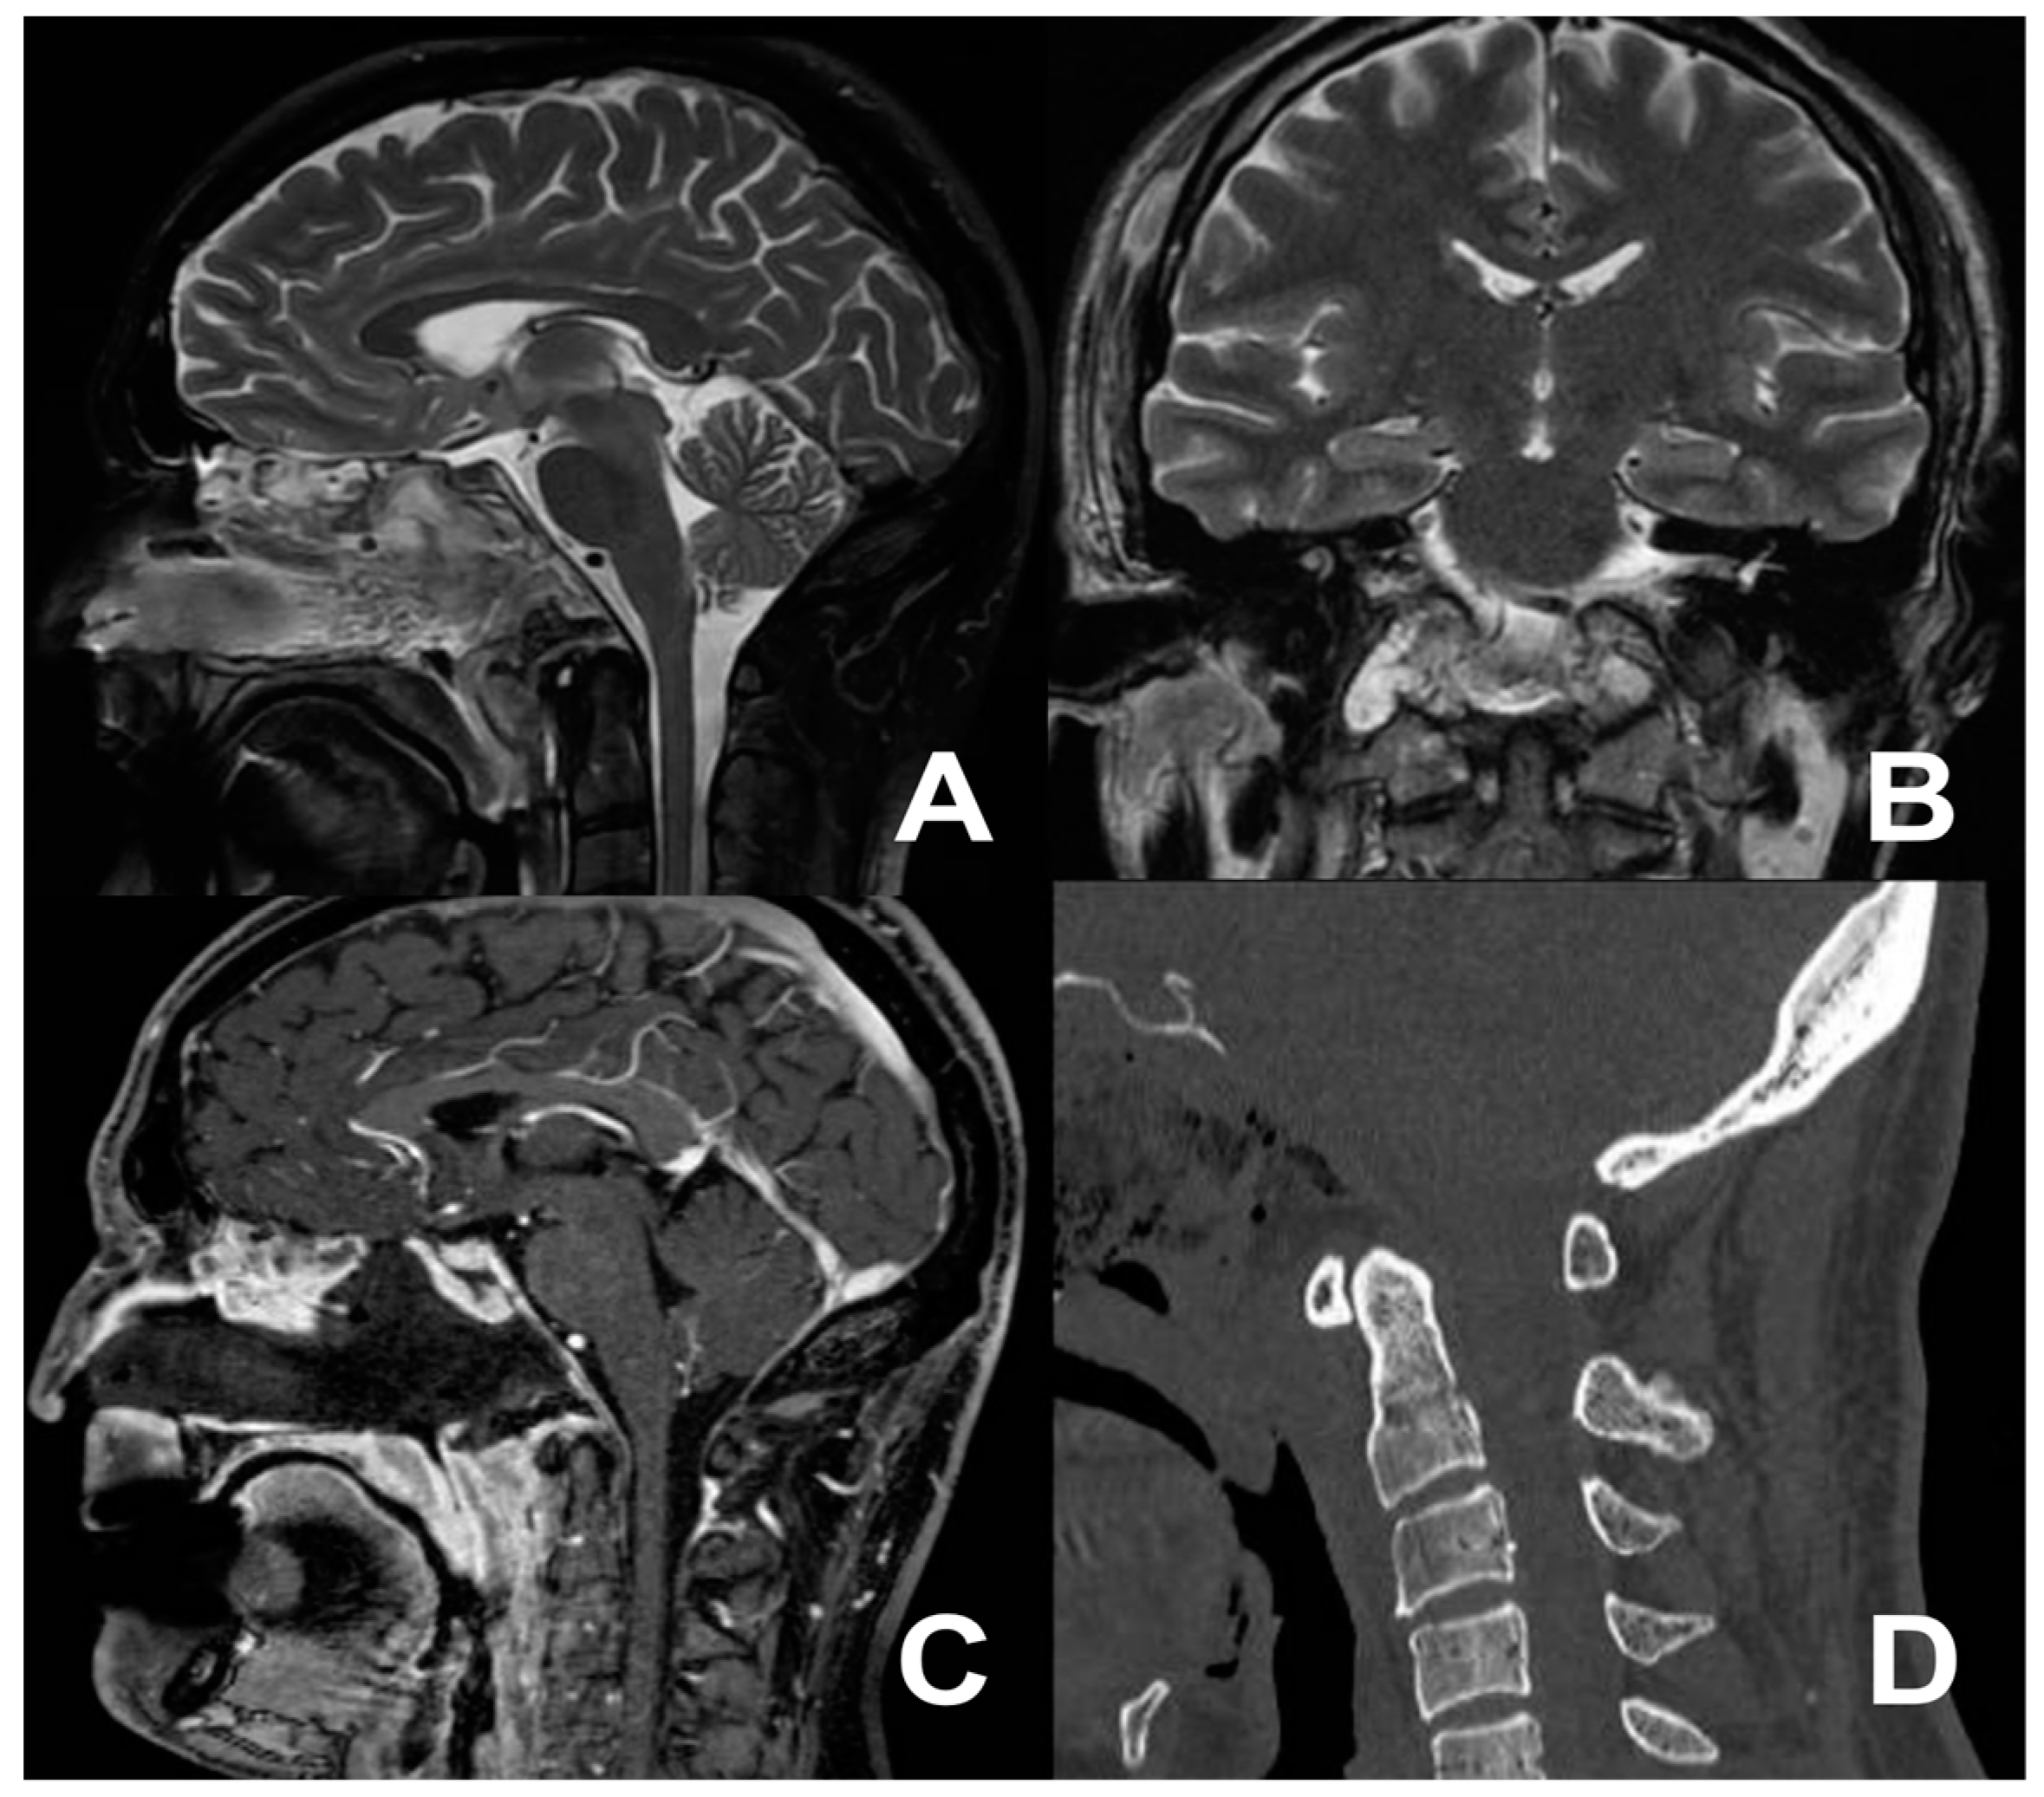

Figure 3.

Postoperative MRI (A–C) and CT scan (D) showing the extent of tumor removal.